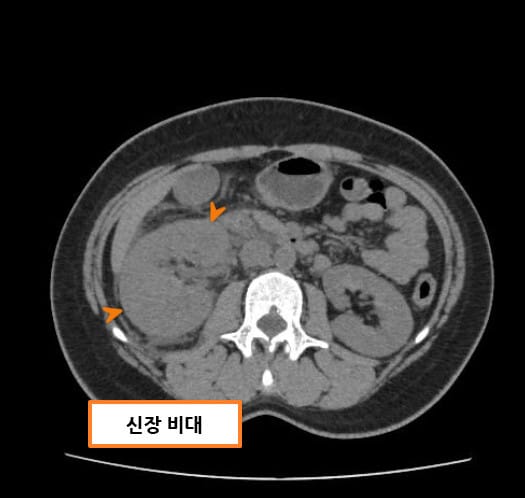

| CT 소견 |

| 🔴 비대칭적 신장 크기 |

| 신정맥 혈전증이 동반되면 혈전이 발생한 쪽 신장이 비대해지고, 혈류가 감소합니다. |

Abdrabou A, Renal vein thrombosis. Case study, Radiopaedia.org (Accessed on 23 Jul 2025) https://doi.org/10.53347/rID-51291